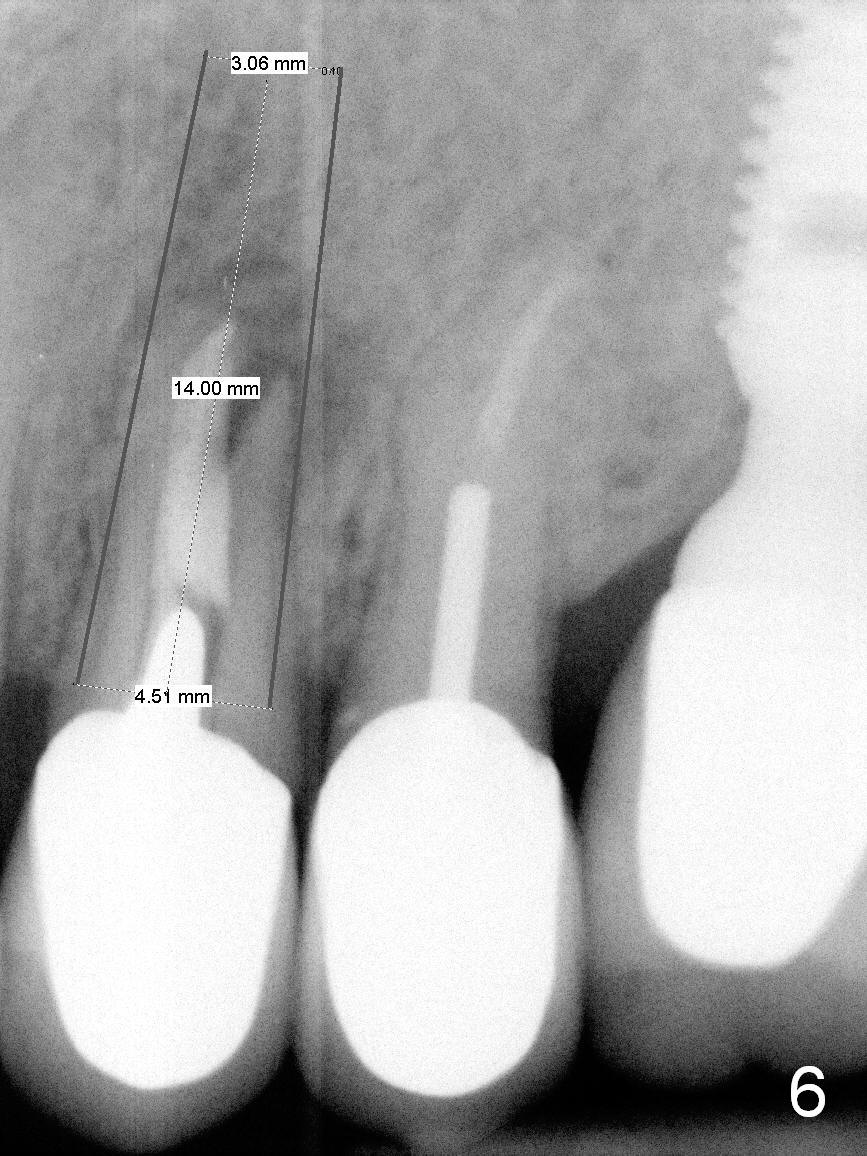

A 4.5x14 mm bone-level or 4.5x17 mm tissue-level implant appears to be appropriate for the site according to the PA (Fig.6,7). CBCT shows that there is enough bone to place a 4.5x20 mm tissue-level implant (Fig.8). This is more appropriate, considering the large radiolucency (Fig.5), the age of the patient (possibly osteoporosis), and the maxilla (bone softer than that of the mandible). The implant will be supported by approximately 8 mm solid bone apically (Fig.8).

In addition, osteotomy will be under prep. The depth of a 2 mm pilot drill, 2.5 mm and 3 mm reamers will be 20 mm, 17 mm and 14 mm, respectively. A 4.5x20 mm tap will be inserted 17 mm before placing the corresponding implant. Intraop PAs are to be taken following the pilot drill, tap and implant.